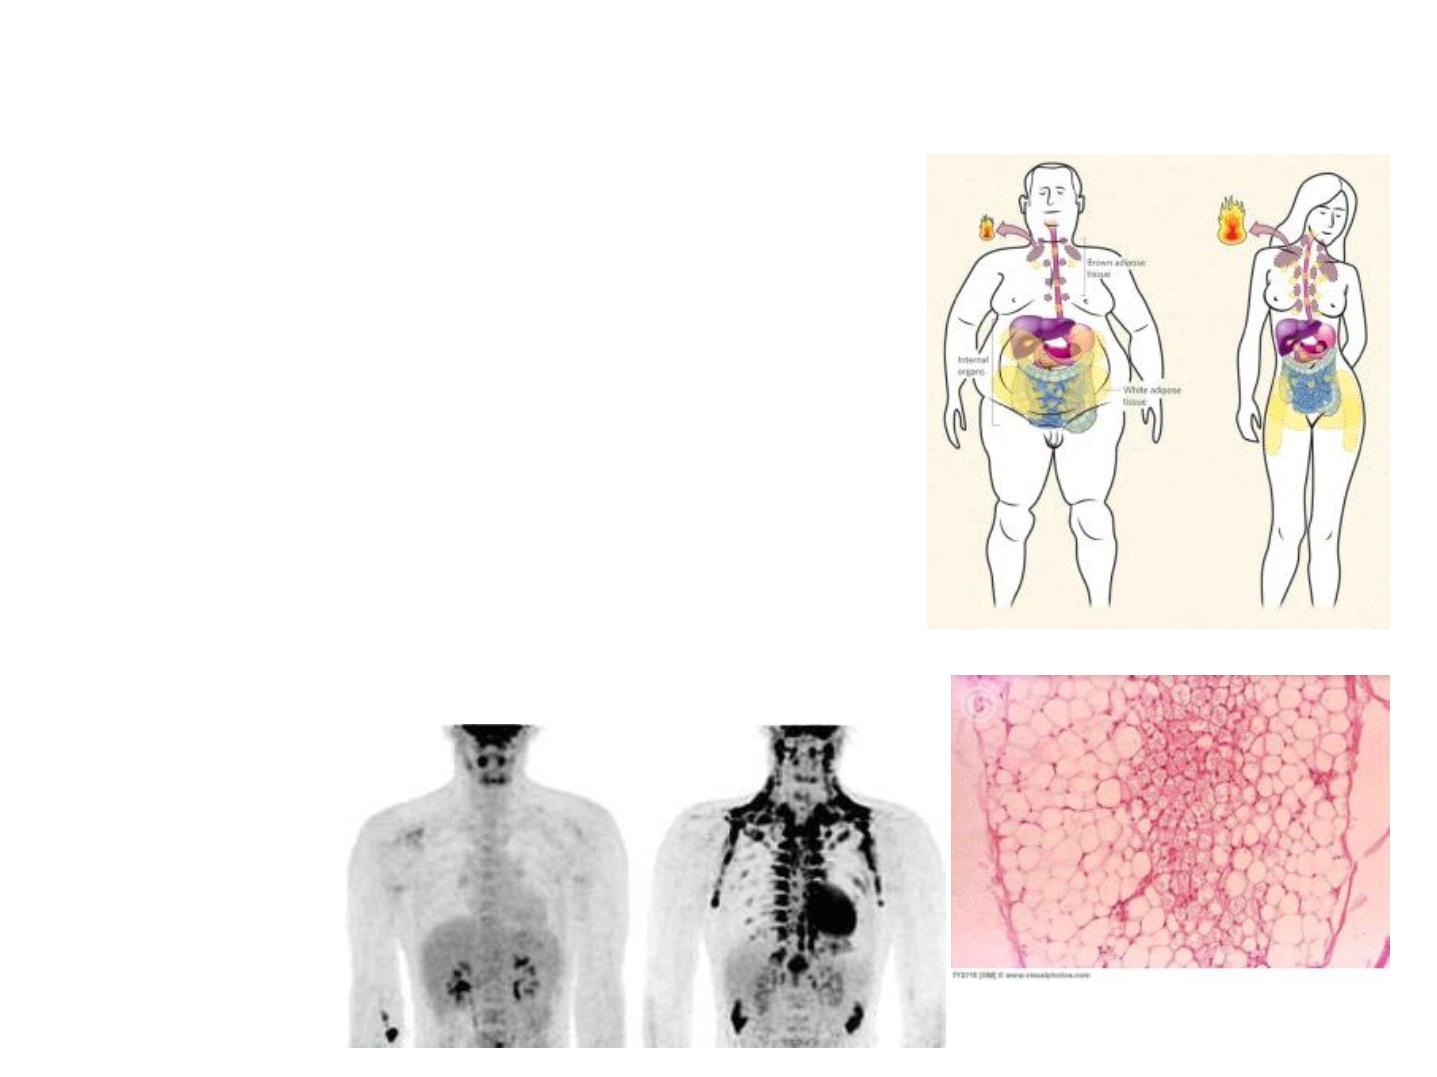

Brown Adipose Tissue

12

• Mainly participates in Thermogenesis

• Located in separate pockets in the

paravertebral, supraclavicular and

periadrenal regions

• Histologically different from WAT

• Multiloculated adipocytes

• Large number of mitochondria (brown

colour)

Brown adipose tissue

• contains cells with multiple lipid droplets interspersed among abundant

mitochondria, which give these cells a darker appearance.

• Both types of adipose tissue have a rich blood supply.

• In humans the amount of brown fat is maximal relative to body weight at birth,

when thermogenesis is most needed and partially disappears by apoptosis and

involution during childhood.

• In adults the amount and activity of brown fat are higher in slim individuals.

• The number of brown adipocytes increases during cold adaptation in adults, usually

appearing as clusters of multilocular cells in white adipose tissue. Besides

stimulating thermogenic activity, autonomic nerves also promote brown adipocyte

differentiation and prevent apoptosis in mature brown fat cells.

• These cells each contain primarily one large lipid droplet (they are unilocular),

causing the nucleus and remaining cytoplasm to be pushed against the

plasmalemma. Brown Adipose Tissue

Brown fat comprises up to 5% of the

newborn body weight but smaller amounts in adults. Adipocytes of this tissue are

typically smaller than those of white fat and contain primarily many small lipid

droplets (they are multilocular) in cytoplasm containing many mitochondria and a

central nucleus.